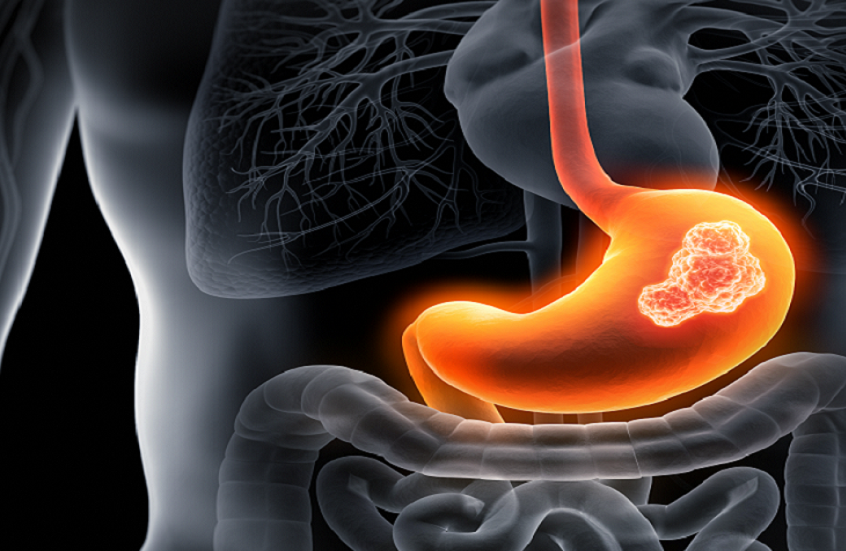

علامات غير نمطية قد تشير إلى سرطان المعدة

يشير الدكتور باسير باماتوف أخصائي الأورام إلى أن بحة الصوت أو السعال طويل الأمد قد يشير إلى الإصابة بسرطان المعدة.

ووفقا له، قد تحدث بعض الأعراض إذا ضغط الورم على العصب الراجع (العصب التائه) أو في حالة وجود نقائل، وتشمل بحة الصوت والسعال لفترة طويلة. كما قد يلاحظ المريض ارتفاعا طفيفا في درجة الحرارة أو تغيّرا في حاسة التذوق.

وفي المراحل المتأخرة، قد تظهر أعراض أكثر وضوحا مثل ألم في الجزء العلوي من البطن، وإمساك وإسهال متناوبان، وقيء مصحوب بدم أو براز أسود ، لذلك يُنصح بمراجعة طبيب مختص فور ظهور أي من هذه الأعراض، حتى ولو كانت غير واضحة أو غير نمطية.